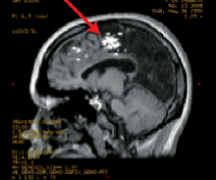

LITT激光间质热疗:针对医学难治性癫痫,目前各种手术技术都在突飞猛进。不同于传统的开颅手术,药物难治性癫痫的手术选择又有了新的“微创”之选——激光间质热疗LITT,该技术可...

打破难治性癫痫的治疗障碍:激光间质热疗LITT技术,有20%~30%的癫痫患者经过长期药物治疗仍不能控制发作,称为“药物难治性癫”,这部分患者中约30%可以通过癫痫外科手术而取得良...

LITT激光间质热疗治疗效果对以下这些疾病的治疗得到了越来越多的证实:1.难治性癫痫2.颞叶癫痫3.海马硬化4.下丘脑错构瘤4.局灶性皮质发育不良等。此外对于胶质瘤、脑膜瘤等脑肿瘤,也...